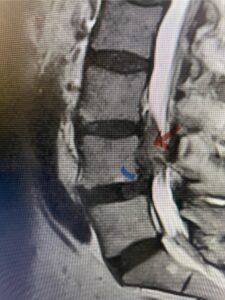

This 54-year-old morbidly obese female presents with progressive back and leg pain and quadriceps weakness. She had no diabetes. She failed all means of conservative management including physical therapy and epidural injections. On imaging she had severe stenosis at L3-4 with a disc protrusion and a slight grade 1 spondylolisthesis at L3-4 (Fig 1). We performed dynamic lumbar x-rays which demonstrated instability at L3-4 and L4-5 (Fig 2). The patient wished to have surgery. We performed an L2-4 decompressive laminectomy and L3-5 in situ fusion because of her instability. Post operatively the patient had relief of leg pain, although the patient was slow to mobilize.

Figs. 1a: Sagittal lumbar T2-weighted MRI demonstrating severe lumbar stenosis with a slight grade 1 at L3-4 and a disc protrusion (red arrow )

Fig 1b: Axial lumbar T2-weighted MRI demonstrating severe lumbar stenosis (red dot)